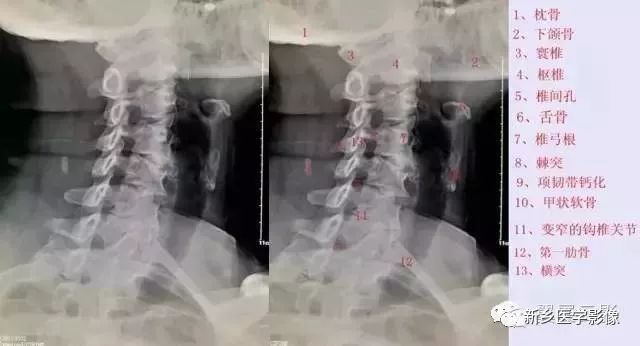

颈椎斜位

拍颈椎双斜位片,主要用来观察椎孔的大小和钩椎关节的骨质增生情况。钩椎关节增生以后,使椎间孔变小,在颈椎斜位片能显示出来,它是产生神经根刺激及椎动脉供血不全的原因。

但是,临床上有些骨质增生明显,并占据椎间孔横径的2/3者也无任何症状。